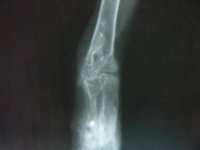

A Once le han quedado unas secuelas irreparables. Los perdigones alojados en su miembro inferior izquierdo han provocado una deformidad en varo de la extremidad y rotación interna. Los primeros días experimentó una reacción defensiva de su organismo a dichos perdigones conocida como granuloma a cuerpo extraño.

No era viable operar puesto que la metralla había fragmentado el hueso. La inflamación provocó a su vez un éstasis vascular y una paresia de la extremidad.

El miembro superior derecho también presentaba una fractura que no pintaba bien, pero con esa sí se atrevió el equipo de veterinarios.

Cuando comenzamos la fisioterapia, Once colaboraba tras las sesiones musculando activamente en la instalación. La metralla limitaba mucho los tratamientos con electromedicina. Casi toda la terapia tenía que ser, por necesidad manual.

Así se fue resolviendo el edema y desrotando la extremidad, aunque la deformidad no era solventable por el daño articular que habían ocasionado los perdigones.